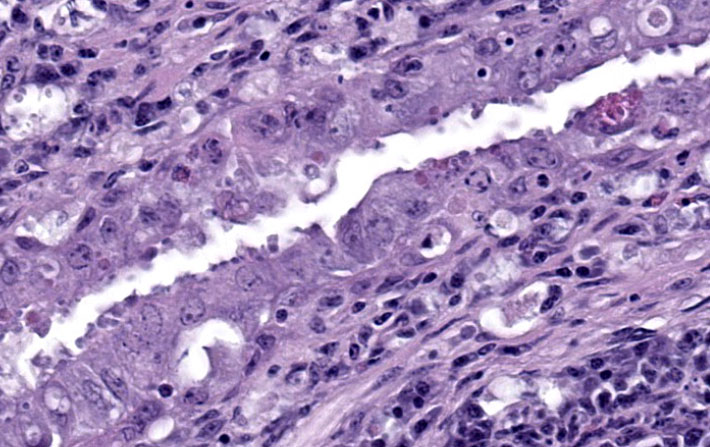

Duodenum: The mucosal lamina propria is markedly infiltrated and expanded by numerous lymphocytes and histiocytes with rare plasma cells. The inflammatory cells broaden and occasionally fuse the villi and separate the intestinal crypts. Within the mononuclear cells are abundant 2 um diameter, basophilic protozoal organisms surrounded by a thin, clear halo that peripheralizes and indents the nucleus. The crypt epithelial cells are often pyknotic and sloughed into the lumen. Epithelial cells at the crypt bases are often hyperplastic, piling three to four cells thick with increased numbers of mitotic figures. The coelomic fat surrounding the duodenum has small, multifocal aggregates of lymphocytes.

Cloaca, colon, and bursa of Fabricius: The lamina propria of the colon is infiltrated and expanded by moderate numbers of lymphocytes and plasma cells that separate colonic crypts. Multifocal crypts are filled with numerous, approximately 5 um diameter, pyriform flagellates with a single, variably distinct nucleus. Similar flagellates are also identified in large numbers within the lumen. Within the bursa of Fabricius, there are similar trichomonad flagellates as well as approximately 2-3 um diameter, round, protozoal organisms that are often adhered to the superficial surface of the epithelial cells.

Flagellates were also present in the colonic and cloacal lumen, including deep in the crypts. In this location, their visualization was complicated by suspected cryptosporidiosis, the third protozoal infection, which was best seen in the bursa of Fabricius. The cryptosporidiosis within the bursa of Fabricius was not confirmed via ancillary diagnostics, but the appearance in this location was typical, though less common than proventricular cryptosporidiosis in passerines. The colonization of the bursa by the Cryptosporidium and the resulting bursitis may have impaired the humoral immune response, further predisposing the starling to the multiple concurrent protozoal infections.

Evaluation of the bursa of Fabricius proved to be an important point of discussion. The bursa naturally involutes as birds age and should be a synchronous process.7 In chickens, the Bursa begins involution around 8-10 weeks of age and is generally heavily involuted by 6-7mo old.7 In this case, however, there was asynchronous depletion of the Bursa, indicating that this was not natural involution. There were some follicles that exhibited lytic central necrosis and lymphocytolysis, demonstrating an active insult to the Bursa that may have contributed to this bird?s immunosuppression. Whether this was viral or parasitic could not be determined. Although participants were not convinced about Cryptosporidium spp., the bursal epithelium are good places to hunt for them since the bursa of Fabricius is a continuation of the intestine. In trying to put a pathogenesis together in this case, participants thought that the most likely primary cause of this bird's demise was nutritional malabsorption due to the marked histiocytic enteritis with epithelial necrosis and crypt separation.